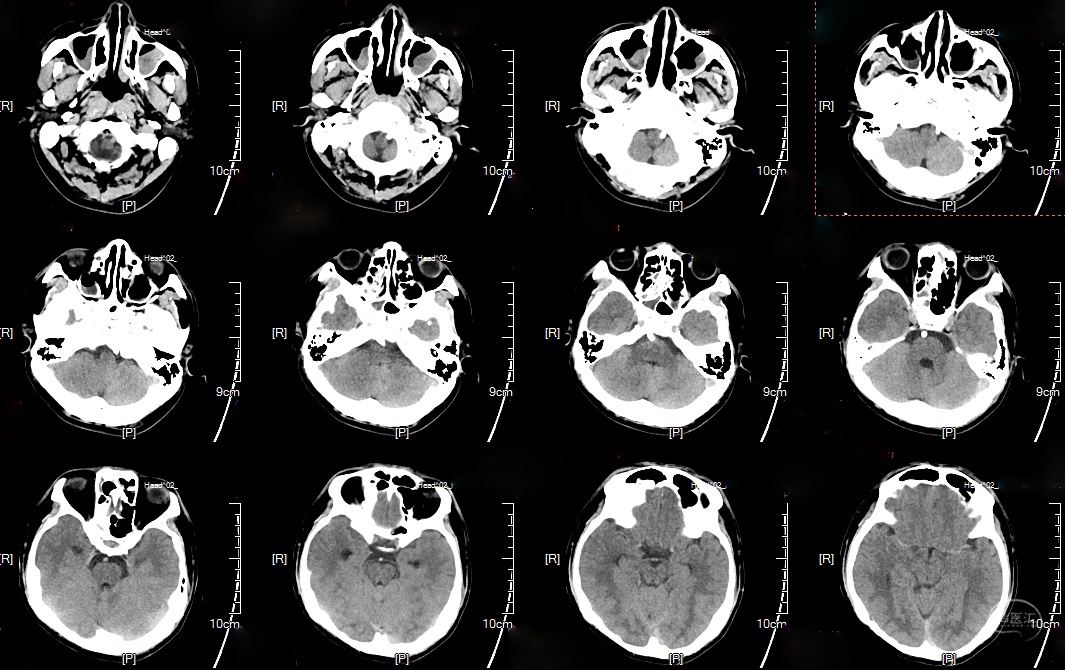

术后头颅CT(2023-10-17):

术后造影显示动脉瘤内造影剂滞留明显,载瘤动脉通畅。

支架CT: